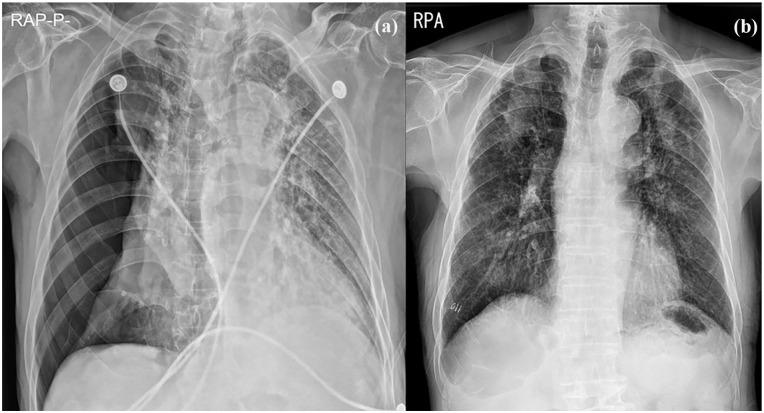

我报告2例老年继发性自发性气胸患者用50%葡萄糖水(DW)进行胸膜融合术。在这两个病例中,胸部计算机断层扫描显示大气胸伴肺气肿和多个大泡。考虑到患者的年龄和潜在的肺部疾病,预计他们不会忍受手术治疗。以前,胸膜固定术是使用其他化学药剂进行的。然而,化学性胸膜穿透术可伴有胸痛、发热,很少伴有呼吸衰竭。2例胸膜截留术,胸膜截留率50%,气胸消退,无并发症。我建议即使是不能耐受手术或化学胸膜固定术的老年患者,也可以考虑使用50% DW胸膜固定术,因为它相对更安全有效。

I report 2 cases of pleurodesis with 50% dextrose water (DW) in very elderly patients with secondary spontaneous pneumothorax. In both cases, a chest computed tomography scan showed a large pneumothorax with emphysema and multiple bullae. Patients were expected not to tolerate surgical treatment, considering their old age and underlying pulmonary disease. Previously, pleurodesis is performed using other chemical agents. However, chemical pleurodesis can be associated with chest pain, fever, and rarely, respiratory failure. Pleurodesis with 50% DW was performed in 2 patients with resolution of pneumothorax without complications. I recommend that even in elderly patients who could not tolerate surgery or chemical pleurodesis, pleurodesis using 50% DW could be considered because it is relatively safer and effective.